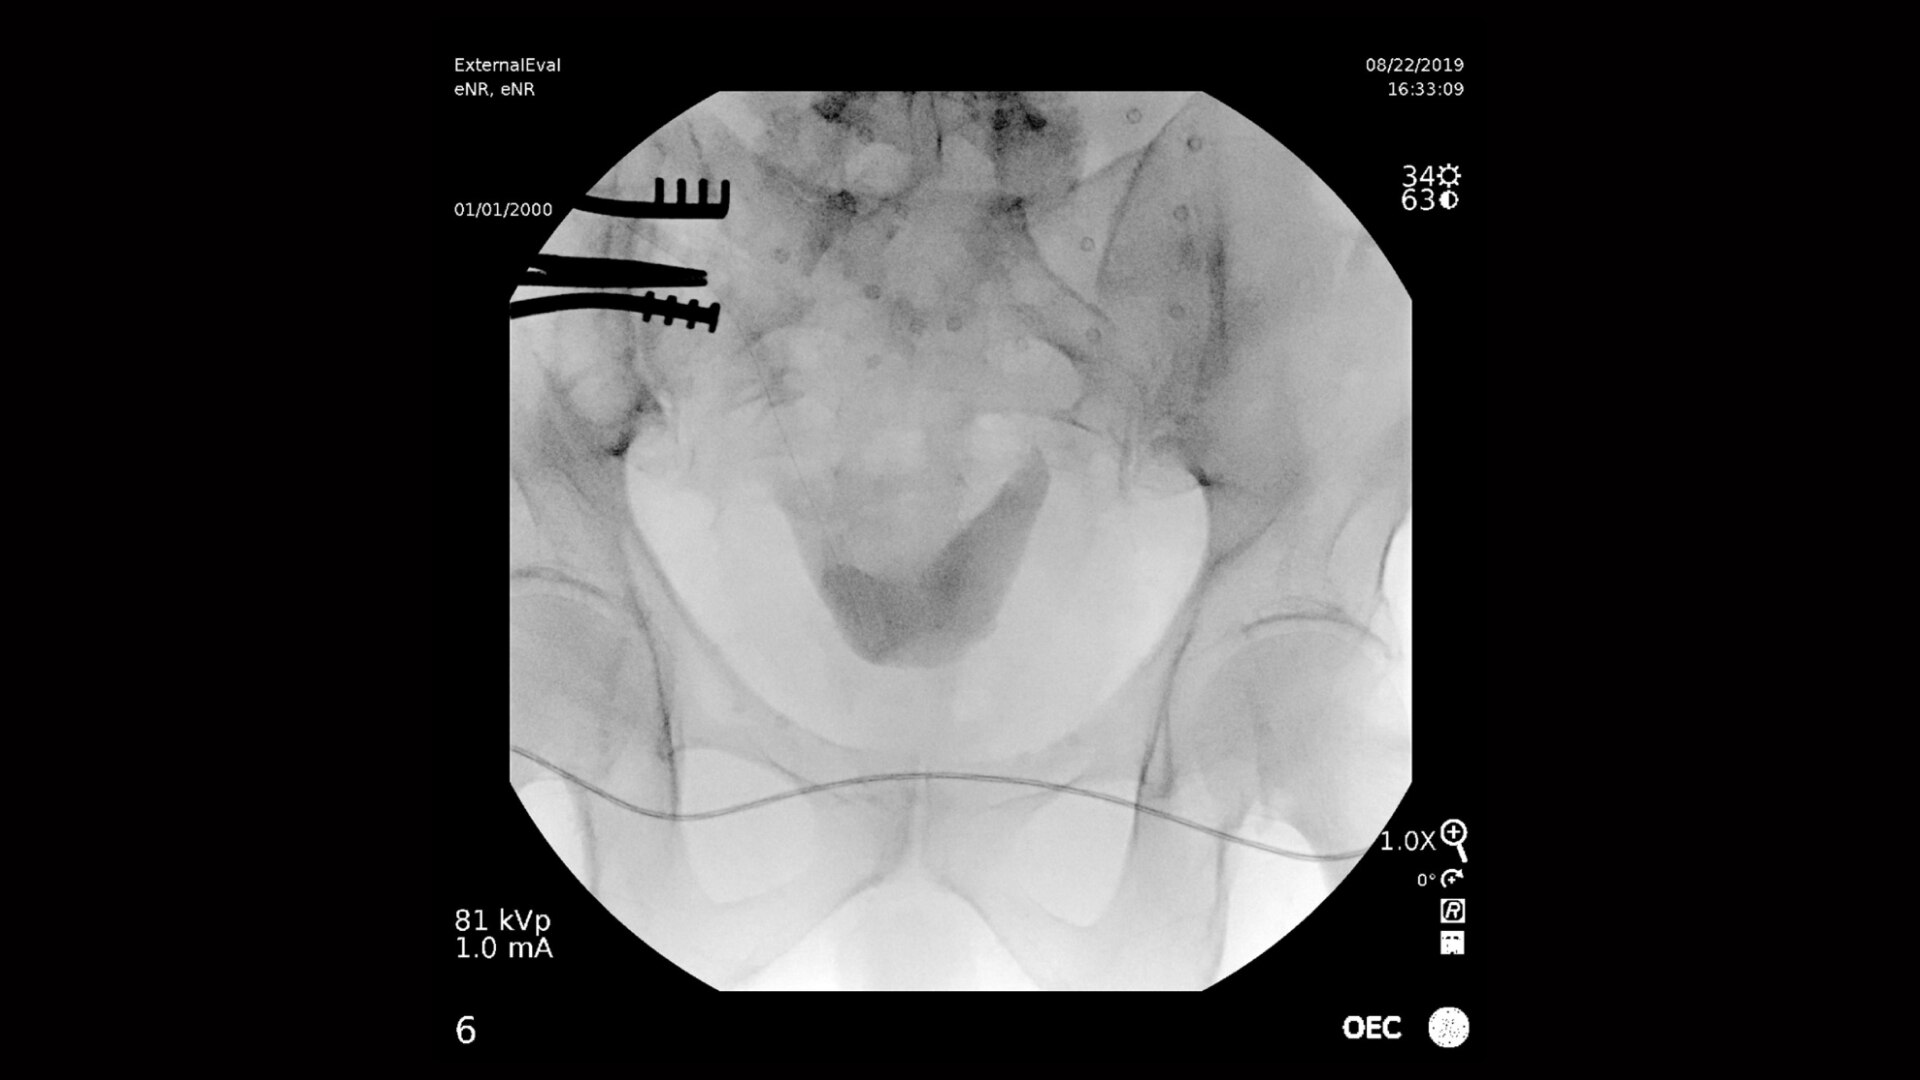

Visualizza in modo chiaro e nitido l'intero tratto urinario, dai reni alla vescica, durante le procedure urologiche. Gli archi a C OEC offrono immagini di qualità eccezionale consentendo ai medici interventisti di identificare facilmente i piccoli dettagli anatomici dell'apparato urinario, come ad esempio le cavità urologiche. Un display nitido con ampio campo visivo fornisce una visualizzazione completa senza la necessità di riposizionare l’arco a C OEC, consentendo un flusso di lavoro più semplice .

Dettagli 1:1 dal detettore al display 4K UHD per immagini di qualità eccezionale e la visualizzazione di tubi di drenaggio a bassa densità e spazzole per biopsia.

Rispetto agli archi a C monoblocco, ottieni un campo visivo più ampio del 22% posizionando il detettore più vicino all'anatomia del paziente con l'alloggiamento del tubo radiogeno a basso profilo OEC.